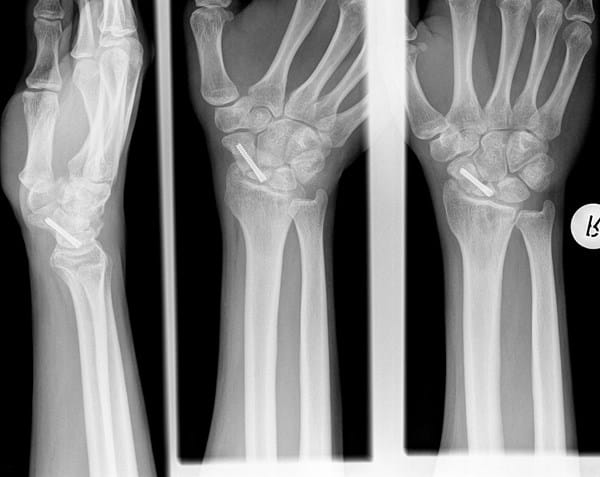

Quería saber, cuál es tu opinión de esta radiografía de una fractura de escafoides que he sufrido?

En Enero me han operado de una fractura de escafoides del polo proximal con un tornillo y un injerto de hueso. El caso es que mi traumatólogo insiste en esperar a ver como evoluciona el hueso hasta Agosto y el médico privado, me ha dicho que me tienen que volver a operar si o si, ¿cuál es vuestra opinión de esta radiografía? Gracias.

Imagen de la radiografía: